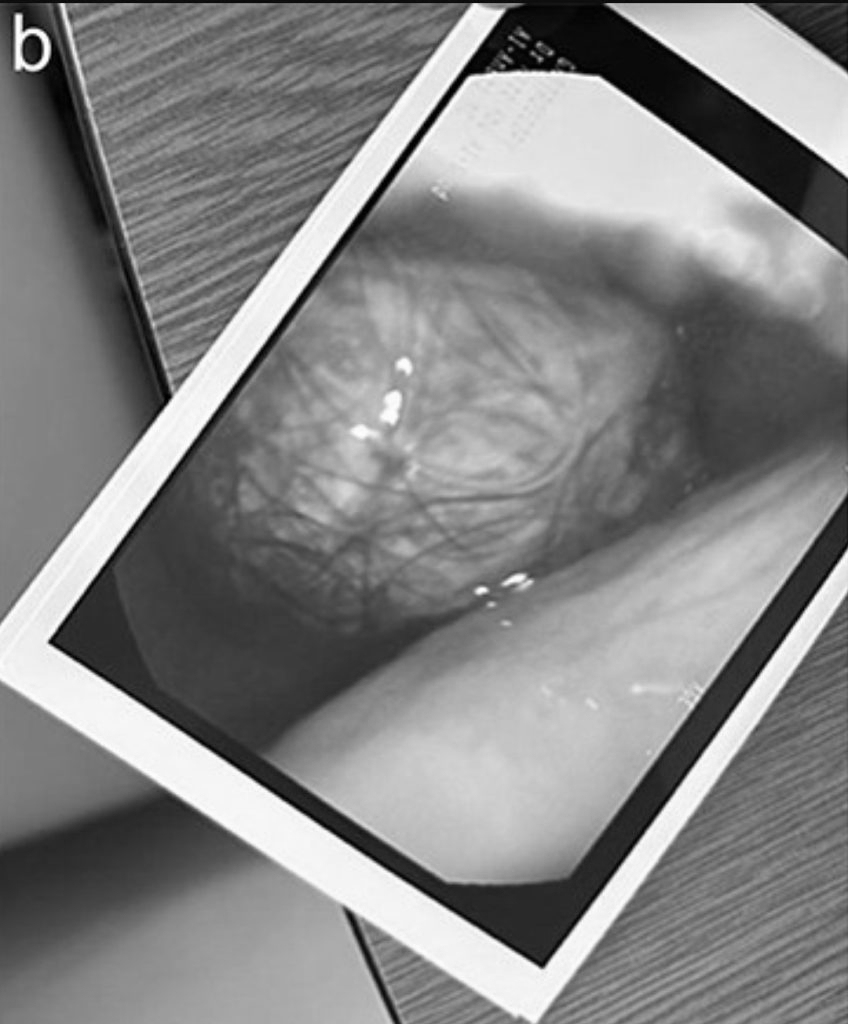

แม้ผลตรวจเลือดและผลแล็บอื่น ๆ จะเป็นปกติ แต่ภาพถ่าย CT scan ชี้ชัดว่าก้อนผมได้ขยายขนาดจากกระเพาะอาหารไปจนถึงลำไส้เล็กส่วนต้น (duodenum)

เนื่องจากขนาดของก้อนผมใหญ่เกินกว่าจะนำออกทางการส่องกล้อง แพทย์จึงตัดสินใจผ่าตัดเปิดช่องท้องภายใต้การดมยาสลบ การผ่าตัดใช้เวลานานประมาณ 3 ชั่วโมง และสามารถนำก้อนผมออกได้อย่างปลอดภัย โดยก้อนผมยังคงสภาพสมบูรณ์